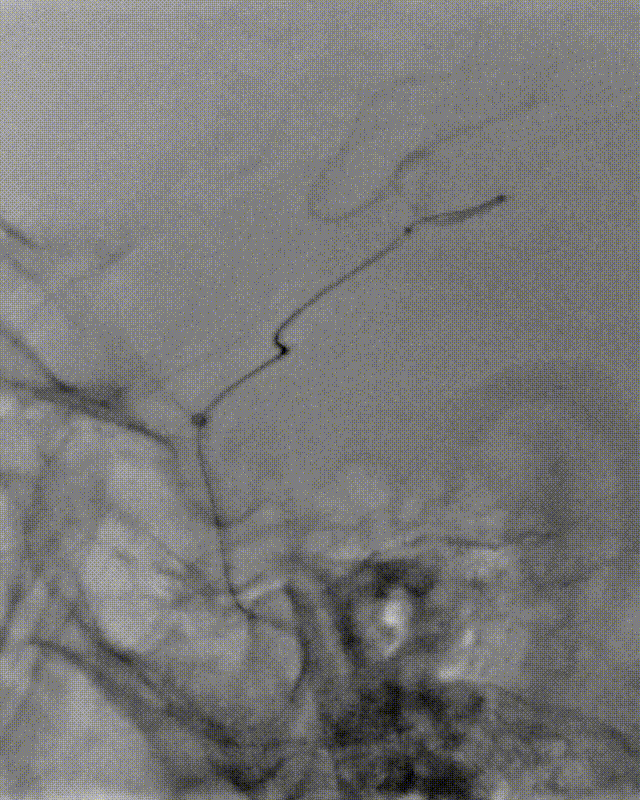

泥鳅导丝、SIM2造影导管、5.5F Introsky X导管鞘同轴下继续跟进,尽可能高到位,随后引入V-18导丝。

什么叫桡鞘【例久弥新】寻道于桡——瑞康通5.5F Introsky X导管鞘经桡取栓一例_https://www.jmylbn.com_新闻资讯_第15张

什么叫桡鞘【例久弥新】寻道于桡——瑞康通5.5F Introsky X导管鞘经桡取栓一例_https://www.jmylbn.com_新闻资讯_第16张